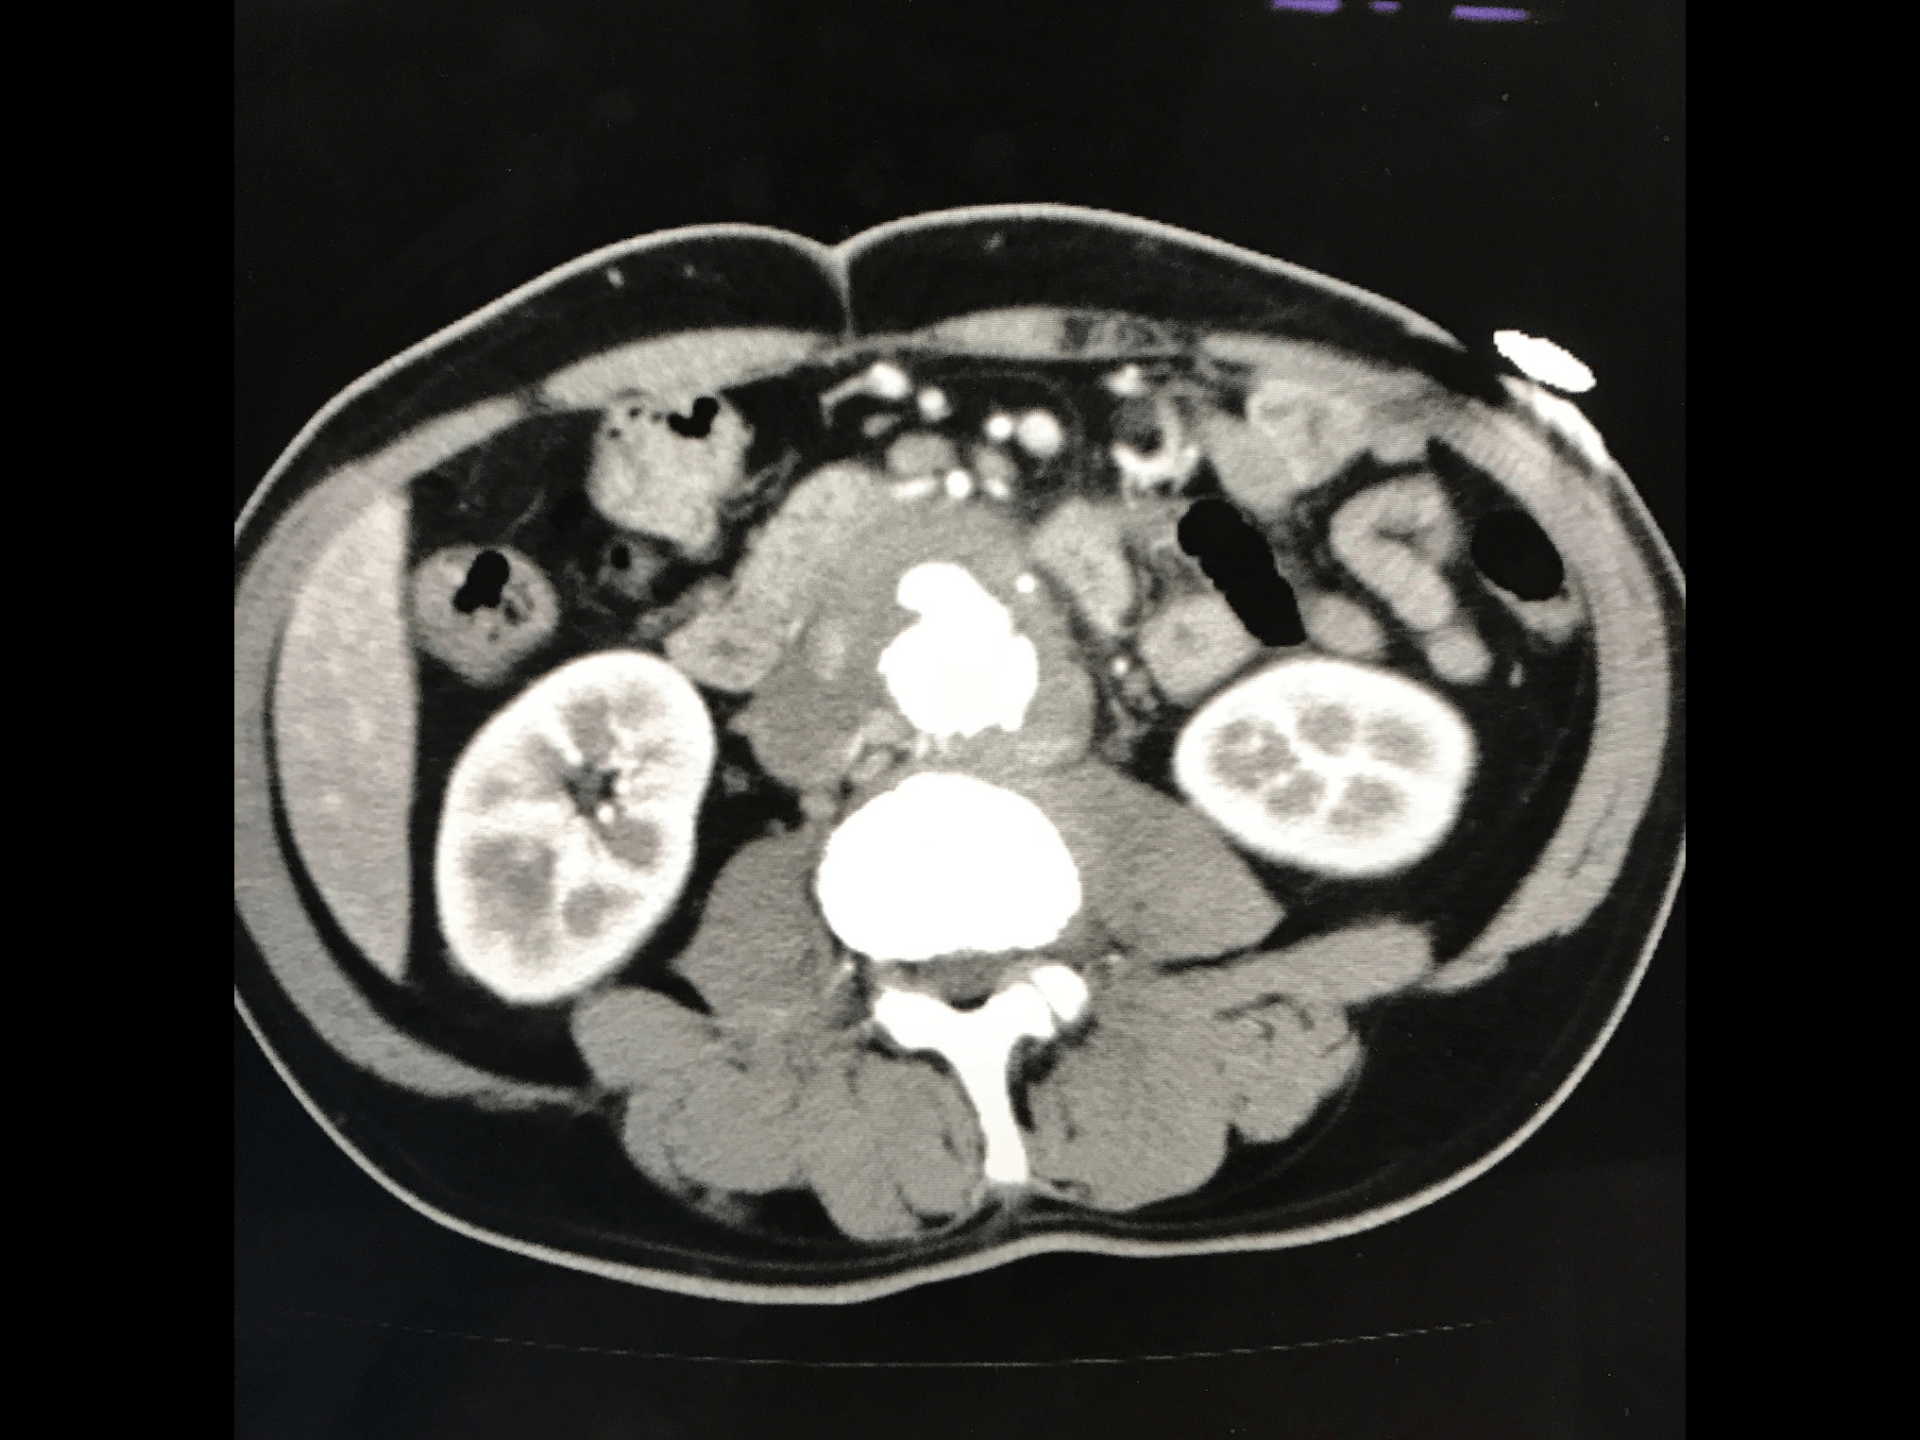

炎症性大動脈瘤(IAAA) 1972年にWalkerらが提唱した概念 Br J Surg 1972; 59:609-614. 腹部大動脈瘤の 5-10 % をしめる Ann Surg 1997; 225: 155-164 厚い動脈瘤壁(1cm以上 J Vasc Surg. 1985;2(6):859 広範な動脈瘤周囲と後腹膜の繊維化 隣接する腹部臓器との癒着 An article from the E-Journal of the ESC Council for Cardiology Practic e ) Vol.7,N°10 - 18 Nov 2008

#7.

炎症性大動脈瘤(IAAA) ①腹痛/背部痛②体重減少③ESR/CRPの上昇 機序は“In ammatory variant”と推定されている 65-90%が有症状(アテローム性は8-18% 25%が拍動性 53%が尿管圧迫 (18-21% 慢性腎障害 術前診断は13-33% An article from the E-Journal of the ESC Council for Cardiology Practic ) e ) fl Vol.7,N°10 - 18 Nov 2008

IgG4関連大動脈瘤 炎症性大動脈瘤の50%はIgG4関連 炎症が強いため外膜が肥厚する(破裂リスクは低い)